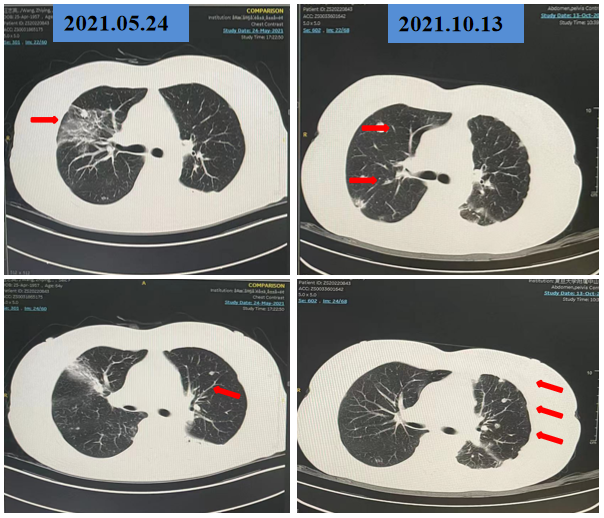

2021-10-13 我院胸部CT:两肺多发结节及团片影,部分较前(2021-5-24)增大,增多;评估:PD。